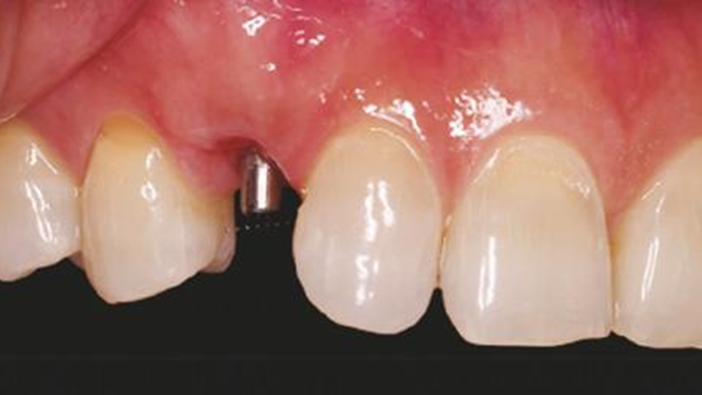

Clinical case: Patient-centered approach: treatment strategy for Root Membrane Technique & delayed implant placement

- Courtesy of Dr. Yoshiharu Hayashi, Japan -

Socket Shield Technique, anterior esthetics, maxillary anterior, esthetic, esthetics, delayed implant placement, socket preservation, AnyRidge, Root Membrane Kit, Root Membrane Technique, Partial Extraction Therapy, PET, esthetic zone, fuse abutment, Dr. Yoshiharu Hayashi,#11,#21,#22

AnyRidge implant system, fuse abutment Root membrane kit, PET Kit